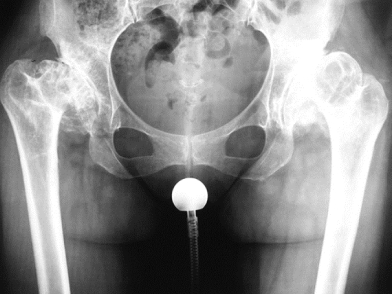

Στους ασθενείς με μη ανατεταγμένα ή μη επάλληλα ισχία και ανεπαρκή κάλυψη της μηριαίας κεφαλής οι οστετομίες διάσωσης της πυέλου, όπως η Chiari και η Shelf, έχουν εφαρμοστεί με σχετική επιτυχία ώστε να καθυστερήσουν την ανάπτυξη τελικού σταδίου οστεοαρθρίτιδας. Ωστόσο, όταν η τελευταία έχει πλέον εγκατασταθεί στην άρθρωση, η θεραπεία εκλογής παραμένει η ολική αρθροπλαστική ισχίου, η οποία μπορεί αξιόπιστα να απαλλάξει τους ασθενείς από τον πόνο και να βελτιώσει τη λειτουργικότητά τους, παρότι έχει συσχετισθεί γενικώς με μεγαλύτερα ποσοστά επιπλοκών σε σχέση με την αρθροπλαστική ισχίου για πρωτοπαθή οστεοαρθρίτιδα. Παρότι στα δυσπλαστικά ισχία αποφεύγεται η εφαρμογή ελάχιστα επεμβατικών τεχνικών αρθροπλαστικής, στην κλινική μας η Μέθοδος ASI χρησιμοποιείται ως τεχνική ρουτίνας και σε αυτές τις περιπτώσεις. Τέλος, η αρθροπλαστική επιφανείας του ισχίου, μία τεχνική αρθροπλαστικής με οικονομικότερη αφαίρεση οστού από την κεφαλή και τον αυχένα του μηριαίου, έχει περιγραφεί επίσης για τα δυσπλαστικά ισχία, αλλά, δεδομένης της συχνότητας της δυσμορφίας του εγγύς μηριαίου σε αυτούς τους ασθενείς, πρέπει να εφαρμόζεται πολύ επιλεκτικά ώστε να αποφευχθεί η υπέρμετρη συχνότητα επιπλοκών.